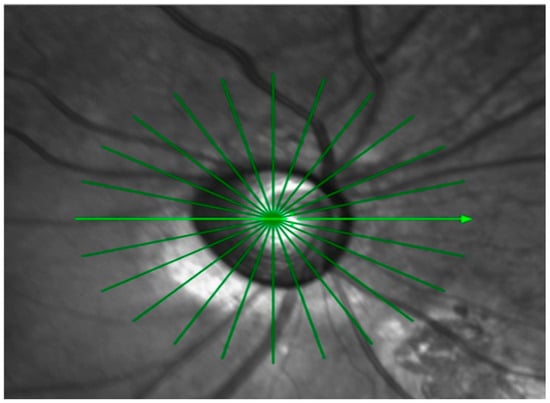

Background/Objectives: Early detection and timely treatment of amblyopia require reliable visual acuity testing in toddlers; however, conventional Landolt ring charts often show poor testability in 2–3-year-old children. Therefore, we aimed to verify the practicality of a new Child-Friendly Minimum-Separable (CFMS) chart for 2–3-year-old children by comparing cooperation rates with the standard Landolt ring visual acuity chart. Methods: A prospective pilot study was conducted on 20 children aged 2 years (30.6 ± 3.2 months) and 20 children aged 3 years (41.8 ± 3.9 months). Right-eye visual acuity was tested in random order using the Landolt ring (four options, 3/5 considered correct) and the CFMS chart (two options, 3/3 considered correct). Test cooperation rates and visual acuity were analyzed. Results: In the 2-year-olds, the cooperation rate was 15% and 75% for the Landolt ring and CFMS chart, respectively (p = 0.0005). Twelve children refused to cooperate with the Landolt ring but cooperated with the CFMS chart; the reverse did not occur. In the 3-year-olds, the cooperation rate was 60% and 90% for the Landolt ring and CFMS chart, respectively (p = 0.031); six children cooperated only with the CFMS chart. The odds ratio for cooperation per additional month of age was 1.34 (95% confidence interval [CI]: 1.12–1.59; p = 0.001) and 1.24 (95% CI: 1.03–1.50; p = 0.026) for the Landolt ring and CFMS chart, respectively. Conclusions: Compared to the Landolt ring, the CFMS chart significantly improves cooperation rates for visual acuity testing in 2−3-year-old children, especially among 2-year-olds.